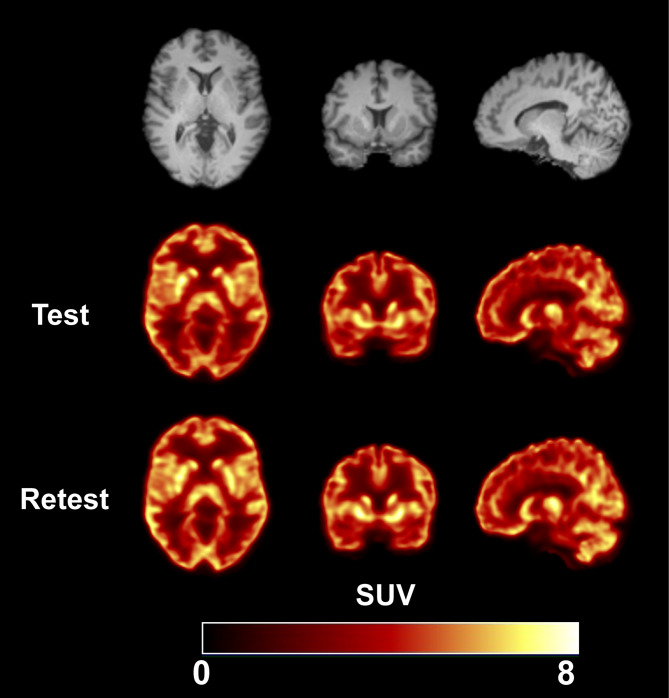

Results: Six participants (3 M/3F) underwent a test-retest scan, each lasting for 120 min using a 4-ring Biograph mCT PET/CT scanner. Arterial blood sampling and metabolite analysis were performed to derive the input function. The two scans were 28 ± 12 days apart (14-43 days, n = 6). Regional time-activity curves (TACs) were generated for 15 regions of interest (ROIs). Kinetic analysis of the 120-min TACs was performed using one-tissue and two-tissue compartment models (1TC, 2TC) and multilinear analysis-1 (MA1) to quantify VT values and compute absolute test-retest variability (aTRV). The effects of scan duration (60 to 120 min) and MA1 t* setting on aTRV and bias were investigated. Careful analysis of the plasma HPLC data was needed since metabolites eluted close in time to the parent. The MA1 model (t* = 40 min) adequately described regional TACs and produced stable kinetic parameters with good agreement to 2TC (MA1 VT=0.98 × 2TC VT + 0.48, bias: -0.1%) while 1TC underestimated VT by 5.1%. Regional VT values exhibited a relatively uniform pattern, highest in the amygdala and lowest in the centrum semiovale. Individual aTRV values ranged from 2 to 9%. Scan durations between 100 and 120 min provided the most consistent results, with minimal bias and acceptable aTRV across all tested t* values. Although a 90-minute scan with t*=10 or 20-minute balanced scan time and aTRV, optimal parameters varied by brain region. Smaller regions (e.g., amygdala) required longer scans to achieve reliable VT quantification.

Abstract Image